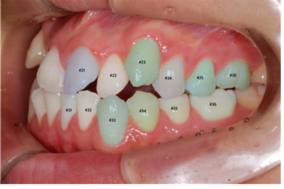

이미지/라벨링 예시

| 이미지 | 라벨링 | |

|---|---|---|

| upper |

치아 경계

| left |

치아경계/치축/대구치관계